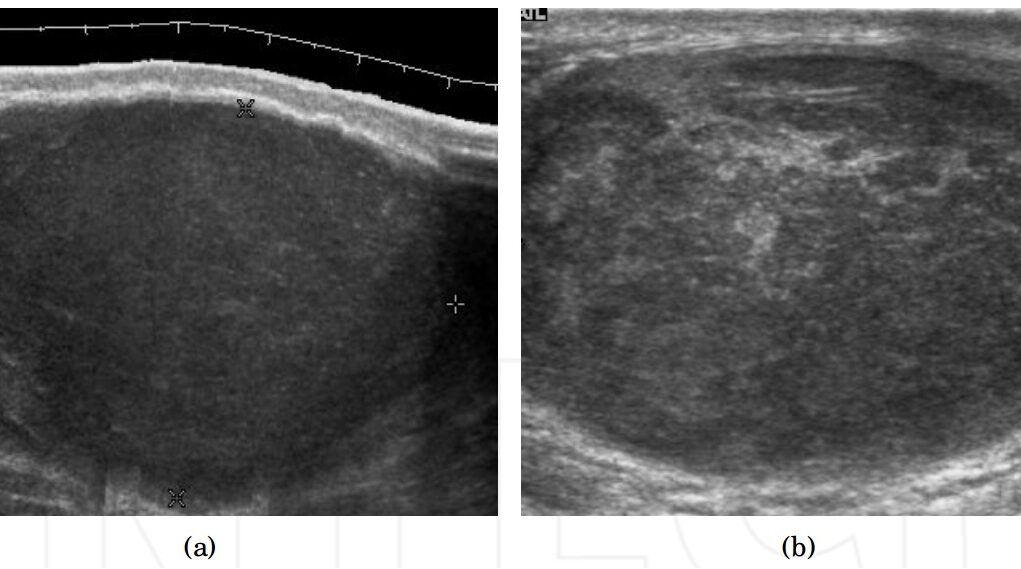

Ormai è risaputo come funziona un’ecografia, esame durante il quale viene applicato un gel sulla superficie interessata e successivamente tramite il passaggio di una sonda vengono emessi ultrasuoni che permettono di creare un immagine dell’interno del nostro corpo.  Un esame facile e indolore svolto in circa 15 minuti tipicamente prescritto in presenza di dolori, infertilità, traumi, palpazione di noduli o come controllo. Permette di individuare diverse patologie molto diffuse tra gli uomini, tra cui varicocele, idrocele, torsione testicolare, epididimite, orchite, cisti, ematomi e tumori. Per quanto non venga usato come test di screening ma come esame di approfondimento, può essere utile fare un controllino una volta ogni tanto per prevenire eventuali problemi, in quanto come abbiamo detto, troppo spesso gli uomini non hanno un buon rapporto con il medico, soprattutto quando riguarda certe zone. Per chiunque voglia cambiare questa regola distorta e lottare per la propria salute, consigliamo di prenotare una Ecografia testicolare a San Lazzaro vicino Bologna presso il poliambulatorio San Lazzaro dove esperti si prenderanno cura di qualsiasi problema.